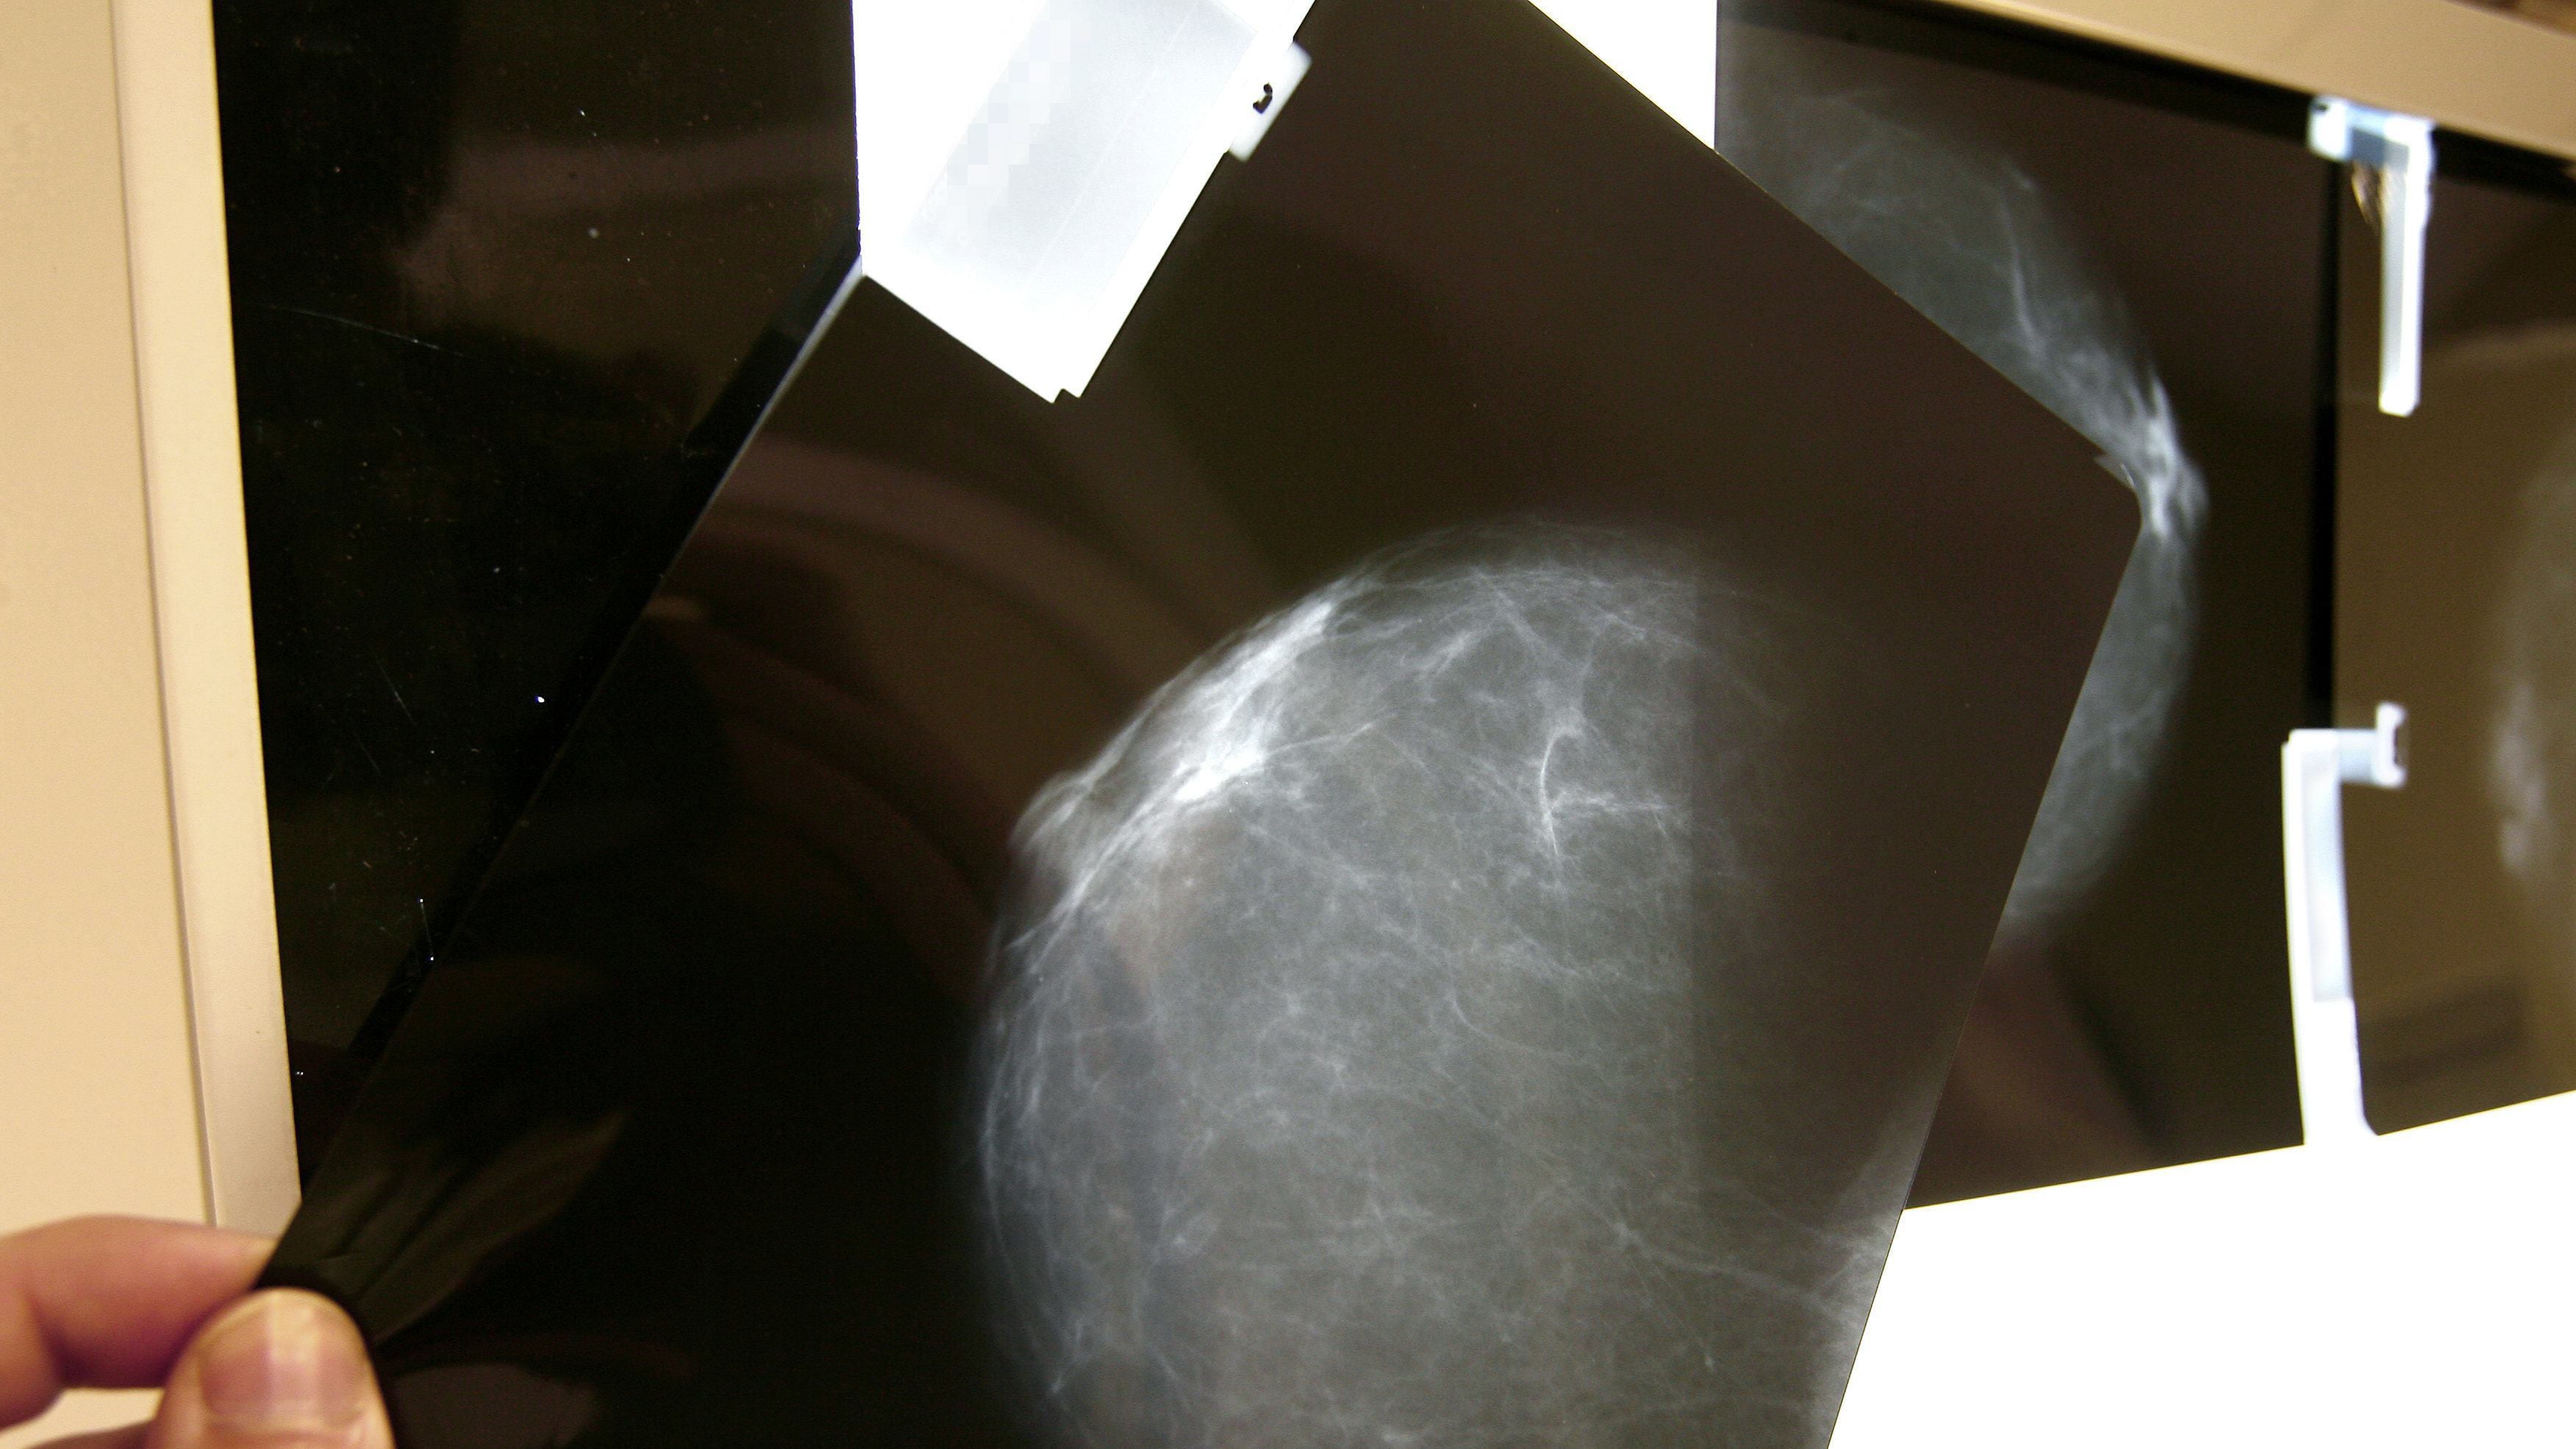

El cáncer de mama en mujeres jóvenes encendió alertas en México, luego de que especialistas señalaran que una proporción significativa de casos se detecta en menores de 40 años, sin protocolos adecuados de diagnóstico temprano.

Miryana Pérez Vela, directora de Fundación de Alba, explicó en entrevista con Publimetro que entre el 11% y el 15% de los diagnósticos anuales de cáncer de mama en el país corresponden a mujeres menores de 40 años.

Este porcentaje, detalló, es superior al registrado en otros países, donde la incidencia en este grupo suele oscilar entre el 7% y el 9%, lo que coloca a México en una situación atípica.